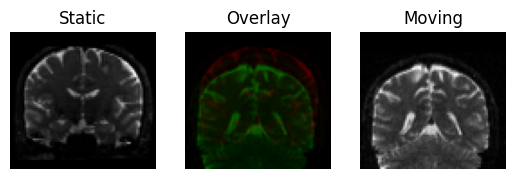

We can obtain a very rough (and fast) registration by just aligning the centers of mass of the two images

We can now transform the moving image and draw it on top of the static image, registration is not likely to be good, but at least they will occupy roughly the same space

Registration result by aligning the centers of mass of the images.